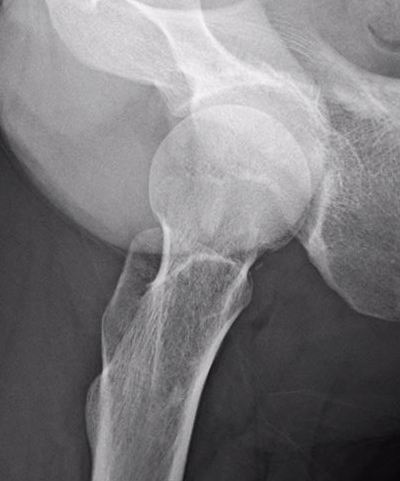

Xray

Shallow cortical defect on the surface of long bones

Periosteal chondromaXray periosteal chondroma